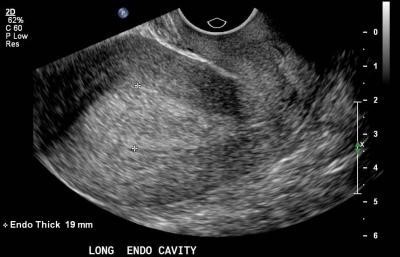

Une échographie pelvienne est indiquée avant de débuter un traitement par tamoxifene afin de dépister une éventuelle anomalie endométriale (sur-risque de cancer de l’endomètre induit par le tamoxifene)

Mme L. n’est pas ménopausée, une hormonothérapie par tamoxifèene est recommandée en première intention. une échographie pelvienne à la recherche d’un épaississement endométrial est recommandée avant de débuter le traitement.

L’examen paraclinique de première intention devant des métrorragies est l’échographie pelvienne par voie sus-pubienne et endocavitaire

L’examen paraclinique de première intention devant des métrorragies est l’échographie pelvienne par voie sus-pubienne et endocavitaire.

Vous réalisez une échographie pelvienne :

En cas de métrorragies post-ménopausique et devant toute épaississement endométrial de manière plus générale, une hystéroscopie est recommandée, associée à un prélèvement, afin de dépister un cancer de l’endomètre. ; L’IRM est indiquée dans le cadre du bilan d’extension de ce cancer lorsqu’il est avéré.